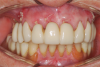

The zirconia provisional was then inserted and evaluated for complete seating, appropriate occlusal contacts, and guidance (Figure 19). No adjustments were needed. A PMMA replica of the zirconia provisional was available as a backup in case adjustment was required.

Lastly, the zirconia provisional was cemented with a polycarboxylate cement, and the patient was reappointed for 1 week to evaluate the occlusion and for follow-up to the surgical procedure (Figure 20 through Figure 23).

Fig 22. The zirconia provisional restoration replicated the patient’s pretreatment restoration.

Figure 22

Fig 23. At 2 weeks postoperatively, the soft tissue was healing nicely around the zirconia provisional.

Figure 23